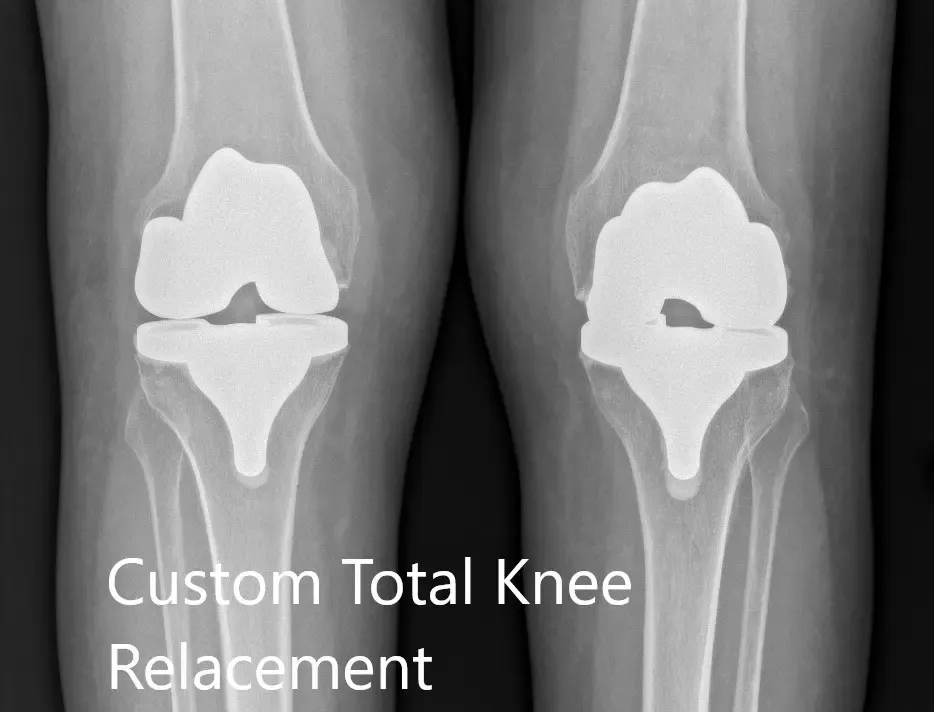

Radiografía postoperatoria que muestra la vista AP de ambas rodillas